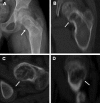

McCune-Albright syndrome (MAS) is classically defined by the clinical triad of fibrous dysplasia of bone (FD), café-au-lait skin spots, and precocious puberty (PP). It is a rare disease with estimated prevalence between 1/100,000 and 1/1,000,000. FD can involve a single or multiple skeletal sites and presents with a limp and/or pain, and, occasionally, a pathologic fracture. Scoliosis is common and may be progressive. In addition to PP (vaginal bleeding or spotting and development of breast tissue in girls, testicular and penile enlargement and precocious sexual behavior in boys), other hyperfunctioning endocrinopathies may be involved including hyperthyroidism, growth hormone excess, Cushing syndrome, and renal phosphate wasting. Café-au-lait spots usually appear in the neonatal period, but it is most often PP or FD that brings the child to medical attention. Renal involvement is seen in approximately 50% of the patients with MAS. The disease results from somatic mutations of the GNAS gene, specifically mutations in the cAMP regulating protein, Gs alpha. The extent of the disease is determined by the proliferation, migration and survival of the cell in which the mutation spontaneously occurs during embryonic development. Diagnosis of MAS is usually established on clinical grounds. Plain radiographs are often sufficient to make the diagnosis of FD and biopsy of FD lesions can confirm the diagnosis. The evaluation of patients with MAS should be guided by knowledge of the spectrum of tissues that may be involved, with specific testing for each. Genetic testing is possible, but is not routinely available. Genetic counseling, however, should be offered. Differential diagnoses include neurofibromatosis, osteofibrous dysplasia, non-ossifying fibromas, idiopathic central precocious puberty, and ovarian neoplasm. Treatment is dictated by the tissues affected, and the extent to which they are affected. Generally, some form of surgical intervention is recommended. Bisphosphonates are frequently used in the treatment of FD. Strengthening exercises are recommended to help maintaining the musculature around the FD bone and minimize the risk for fracture. Treatment of all endocrinopathies is required. Malignancies associated with MAS are distinctly rare occurrences. Malignant transformation of FD lesions occurs in probably less than 1% of the cases of MAS.